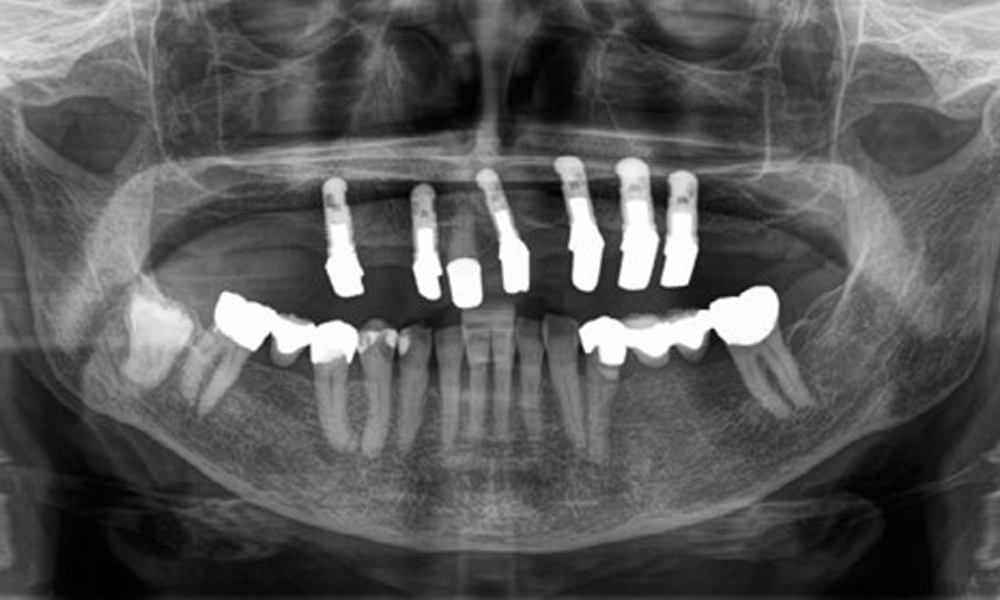

Radiological findings

The radiological findings show partially edentulous dentition with maxillary implants for teeth 15, 13, 21, 23, 24, 25 and a telescopic crown on tooth 11. Adequate mandibular bridges spanning 37 to 34 and 45 to 47 are present. 48 is impacted. There are suspected secondary caries distally on 43 and mesially on 44. 44 is restored with a non-radiopaque cavity lining. There is generalised horizontal bone loss of approx. 10% to 30% and localised vertical bone loss affecting teeth 22 and 42 (Fig. 5).

Panoramic X-ray image. The patient has a full set of adult teeth with generalised bone loss of between 10% and 30%. There is radiological suspicion of secondary caries on 44 and 43.

Fig. 5: Panoramic X-ray image. The patient has a full set of adult teeth with generalised bone loss of between 10% and 30%. There is radiological suspicion of secondary caries on 44 and 43.